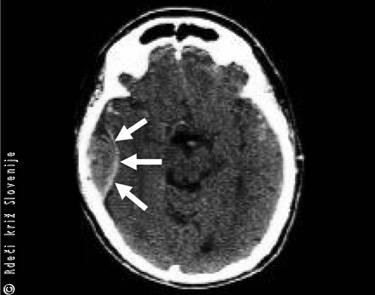

Slika 6

A – Shematski prikaz mesta nastanka možganske krvavitve.

B – Vzrok za nastanek možganske krvavitve – razpok arterije v možganih, ki ima spremenjeno steno žile (mikroanevrizma) zaradi povišanega krvnega tlaka.

C – Računalniška tomografija možganske krvavitve.